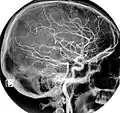

The common carotid artery and its main branches